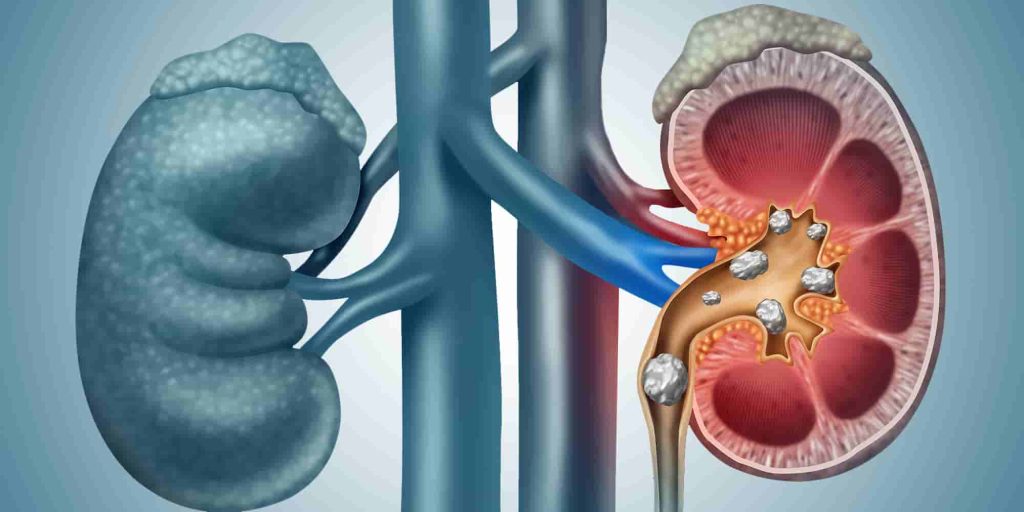

سنگ هاي کلیوي ذرات کوچک و سختی هستند که در یک یا در دو کلیه تشکیل شده و گاهی به داخل حالب ها ( لوله هاي عضلانی باریکی که ادرار را از کلیه ها به مثانه منتقل می کنند ) انتقال می یابند.

شناخت انواع سنگ ھای کلیه

سنگ کلیه شاخ گوزنی (stag horn)

عوارض سنگ کلیه: چه مشکلاتی میتواند ایجاد کند؟

انسداد شدید مجاري ادرار

ھیدرونفروز